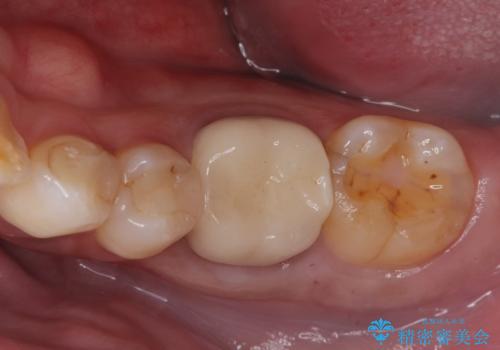

銀歯がとれた セラミックインレーで修復

- 銀歯が取れたとのことで来院されました。

拡大鏡下で丁寧に虫歯を取り除き、セラミックインレーによる修復治療を行いました。

銀歯を固着するセメントは経年劣化し溶け、隙間ができます。そこにプラークが侵入して虫歯が再発します。今回のように銀歯が脱離してしまうこともあります。

今回は銀歯が取れたので、虫歯が神経まで達して痛みが出る前に、強度・審美に優れ、虫歯の再発の少ないセラミックインレーにて治療を行うことができました。